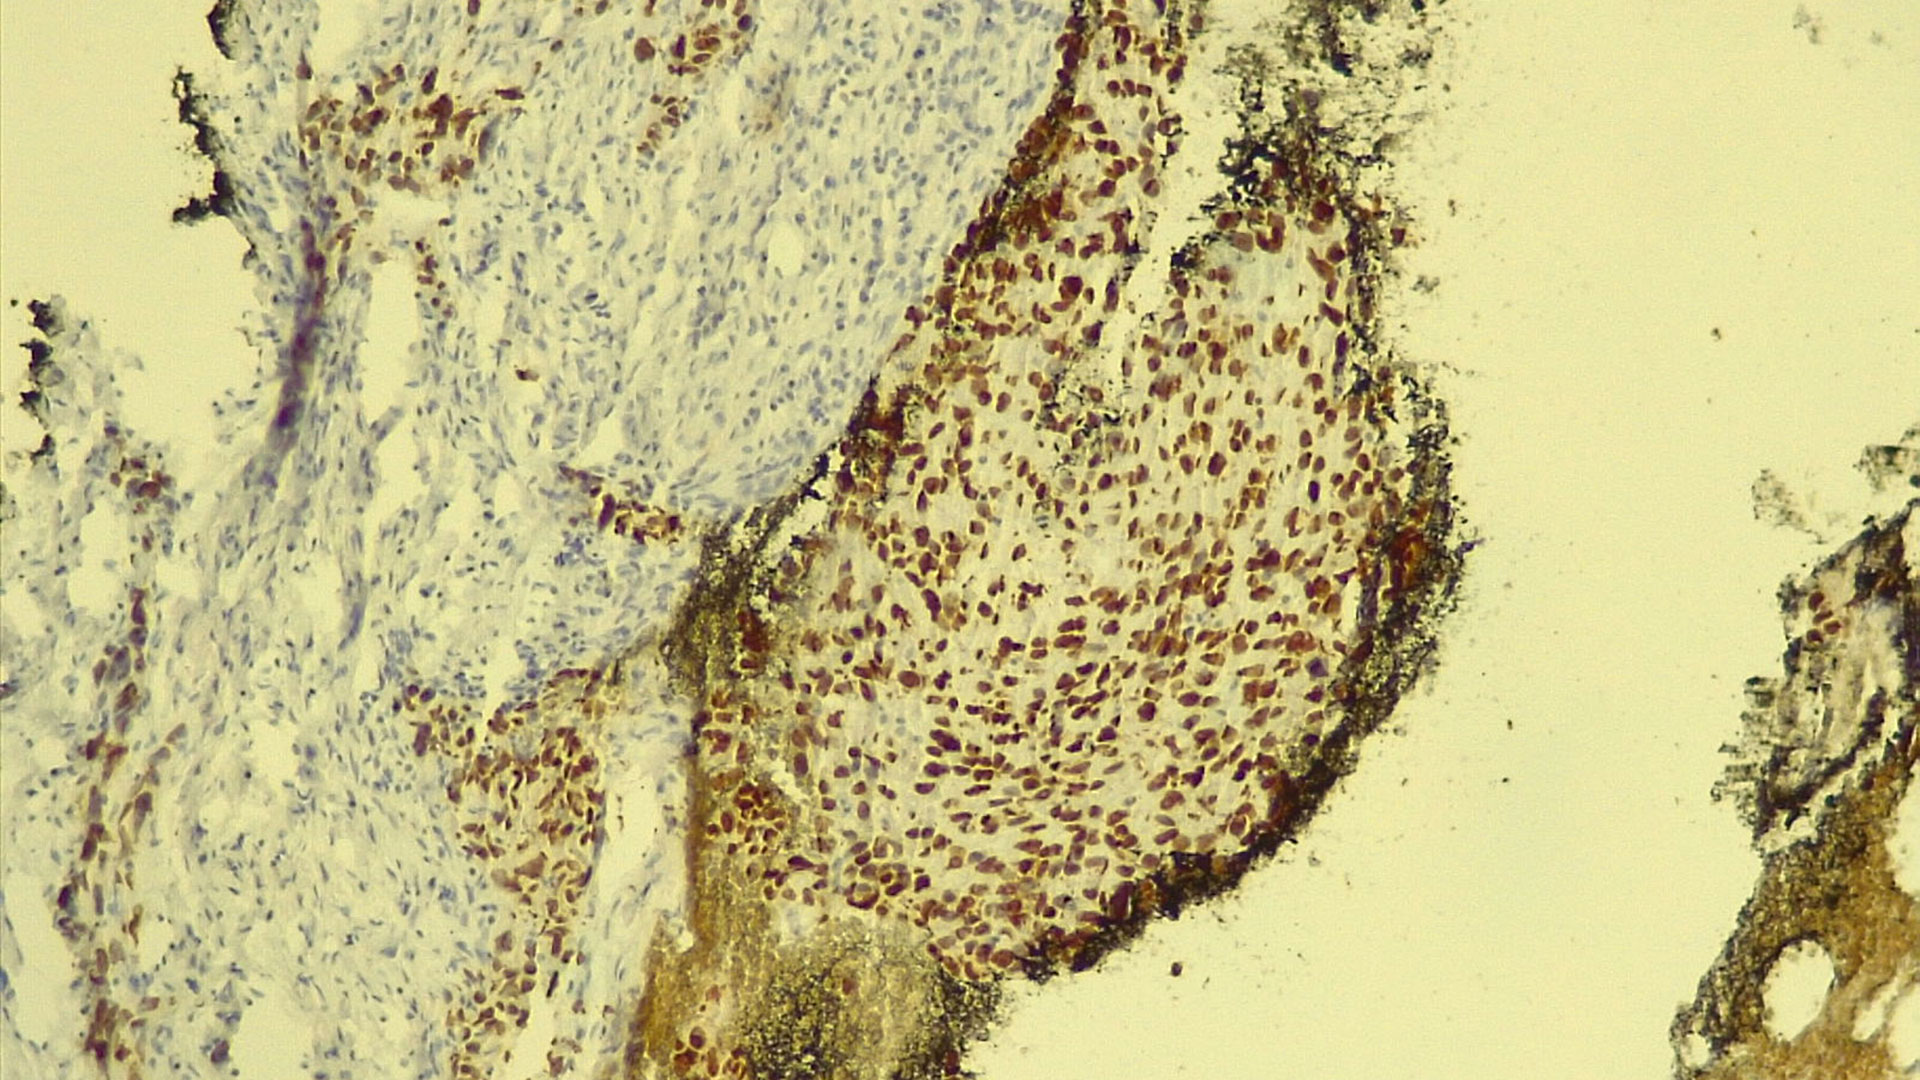

În cadrul Laboratorului de Anatomie Patologică se realizează teste de imunohistochimie (IHC) pe tumori pulmonare primare (care se dezvoltă inițial în plămân), având ca scop diferențierea tipurilor histopatologice de cancer. Metoda aplicată este una manuală și permite, în urma folosirii unor reactivi, evidențierea pe lama de microscopie a unor molecule care ajută la definitivarea diagnosticului de cancer bronhopulmonar. Mai mult, realizarea diagnosticului diferențial și specific de imunohistochimie scurtează timpul de așteptare și permite inițierea unui tratament oncologic personalizat.

“Când vorbim de imunohistochimie (IHC), vorbim de metode de diagnostic care combină tehnica histologică cu cea imunologică și cu biochimia. Practic, IHC-ul este o analiză de laborator care vine în completarea examenului histopatologic. Acesta din urmă stabilește că este vorba de o tumoră, iar imunohistochimia ne dă informații despre caracterul sau tipul formațiunii maligne. În funcție de rezultat, de tipul de tumoră, se administrează tratamentul. Este un proces de diagnosticare în mai mulți pași prin care se identifică markerii tumorali”, spune dr. Gheorghe-Emilian Olteanu – medic specialist anatomie patologică – Spitalul de Boli Infecțioase și Pneumoftiziologie Dr. Victor Babeș Timișoara.

În cazul tumorilor pulmonare, imunohistochimia duce la stabilirea cu precizie a unui diagnostic pozitiv și diferențial.

“Primul pas pentru realizarea examenului de imunohistochimie este prelevarea unui fragment de țesut tumoral, care se realizează în cadrul spitalului nostru făcând biopsie pulmonară. Bucățile de țesut extrase sunt introduse în parafină pentru conservarea lor. Din acestea tăiem secțiuni foarte fine pe care le analizăm sub microscop într-o primă faza, iar, apoi, le supunem examenului IHC. Rezultatul final este unul de precizie”, explică dr. Gheorghe-Emilian Olteanu – medic specialist anatomie patologică – Spitalul de Boli Infecțioase și Pneumoftiziologie Dr. Victor Babeș Timișoara.